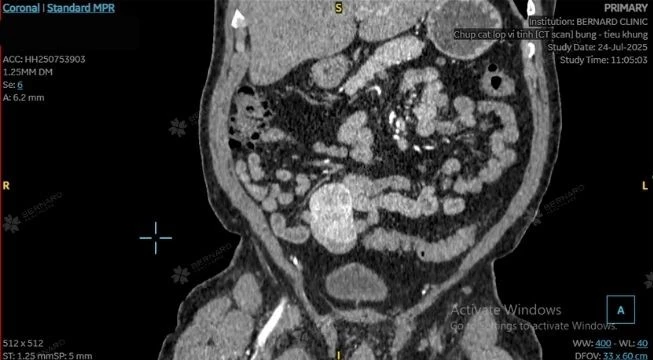

Cùng đánh giá nam khách hàng có nhiều yếu tố nguy cơ về tuổi tác, thói quen sinh hoạt, tiền căn bệnh lý liên quan nội tiết, chuyển hóa và tiêu hóa gan mật, bác sĩ Bernard đã tư vấn bệnh nhân chụp cắt lớp vi tính (CT Scan) bụng - tiểu khung có cản quang nhằm xác định rõ tính chất khối u và mức độ ảnh hưởng đến cơ quan lân cận.

Hình ảnh CT cho thấy tổn thương choán chỗ lớn vùng hố chậu phải, có kích thước 40 x 47 x 65mm (ngang x trước x sau), giới hạn bờ rõ, không xâm lấn xung quanh. Những đặc điểm trên phù hợp với u mạc treo (mesenteric tumors).